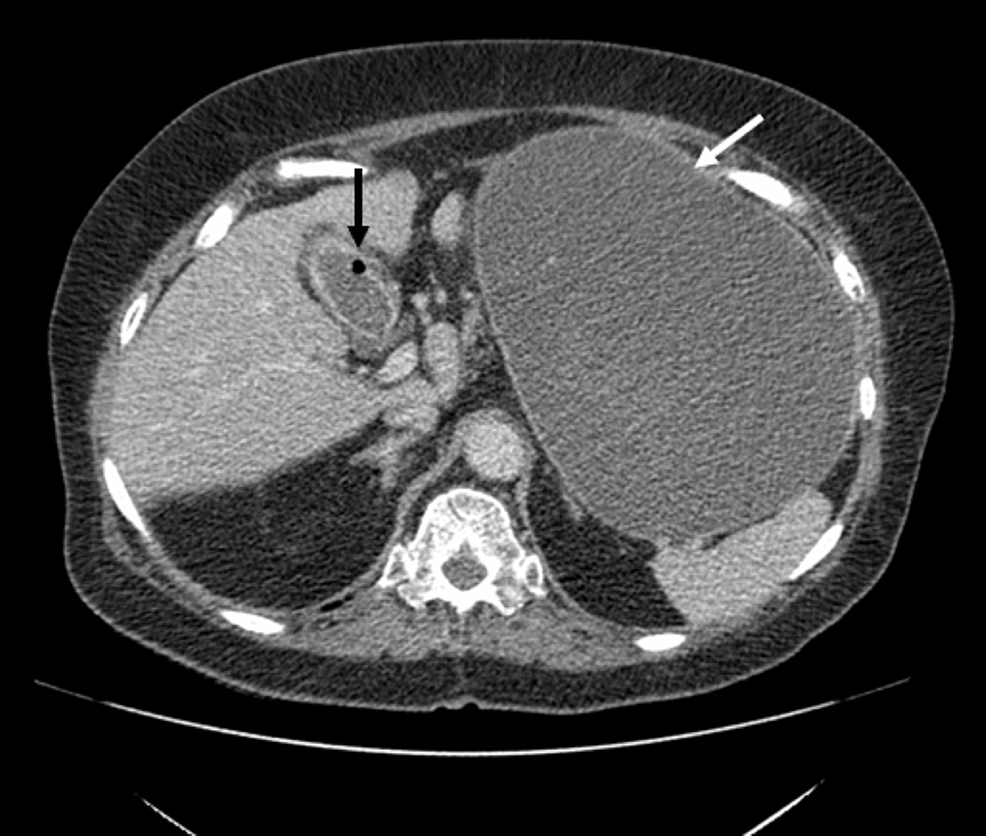

On day 5 of admission, her AKI had improved significantly; with laboratory results showing urea of 4.2 mmol/L, creatinine of 53 µmol/L, and eGFR of 86 mL/min/1.73 m2. A CT thorax, abdomen, and pelvis (CT TAP) was performed and it revealed a gallstone ileus with distal small bowel obstruction. Her gallbladder containing air had collapsed with a large fistula communicating with the duodenal cap. There were two non-obstructing stones within the second and third part of the duodenum; two gallstones in a loop of small bowel within the pelvis; and finally, a large laminated stone measuring approximately 3.7 cm, which was causing bowel obstruction with small bowel loops fluid-filled and dilated proximal to it (Figures 5–7). On the same day, she was operated on and had an exploratory laparotomy, an enterotomy, and the extraction of three gallstones. The gall bladder was left without intervention.